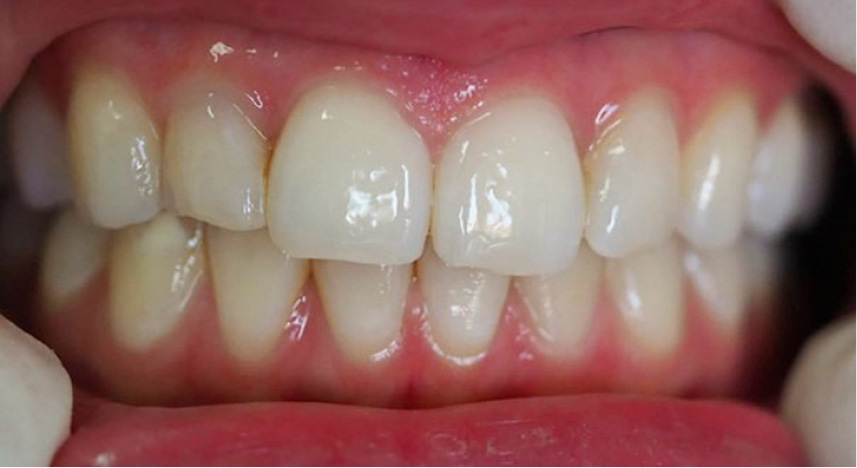

STRESZCZENIE: Próchnica początkowa obserwowana jako biała plama w obrębie szkliwa jest często spotykanym problemem w praktyce klinicznej. Prawidłowa diagnostyka i wdrożenie leczenia za pomocą systemu Icon mogą niejednokrotnie okazać się skutecznymi narzędziami walki z tym problemem. Praca zawiera opis przypadku leczenia zmiany na zębie 43 poprzez infiltrację.

SUMMARY: Initial caries, seen as a white enamel spot, is a common problem in clinical practice. Proper diagnostics and the implementation of treatment using the Icon system can often prove to be an effective tool to combat this problem. The article describes a case of treating a lesion on tooth 43 by infiltration.